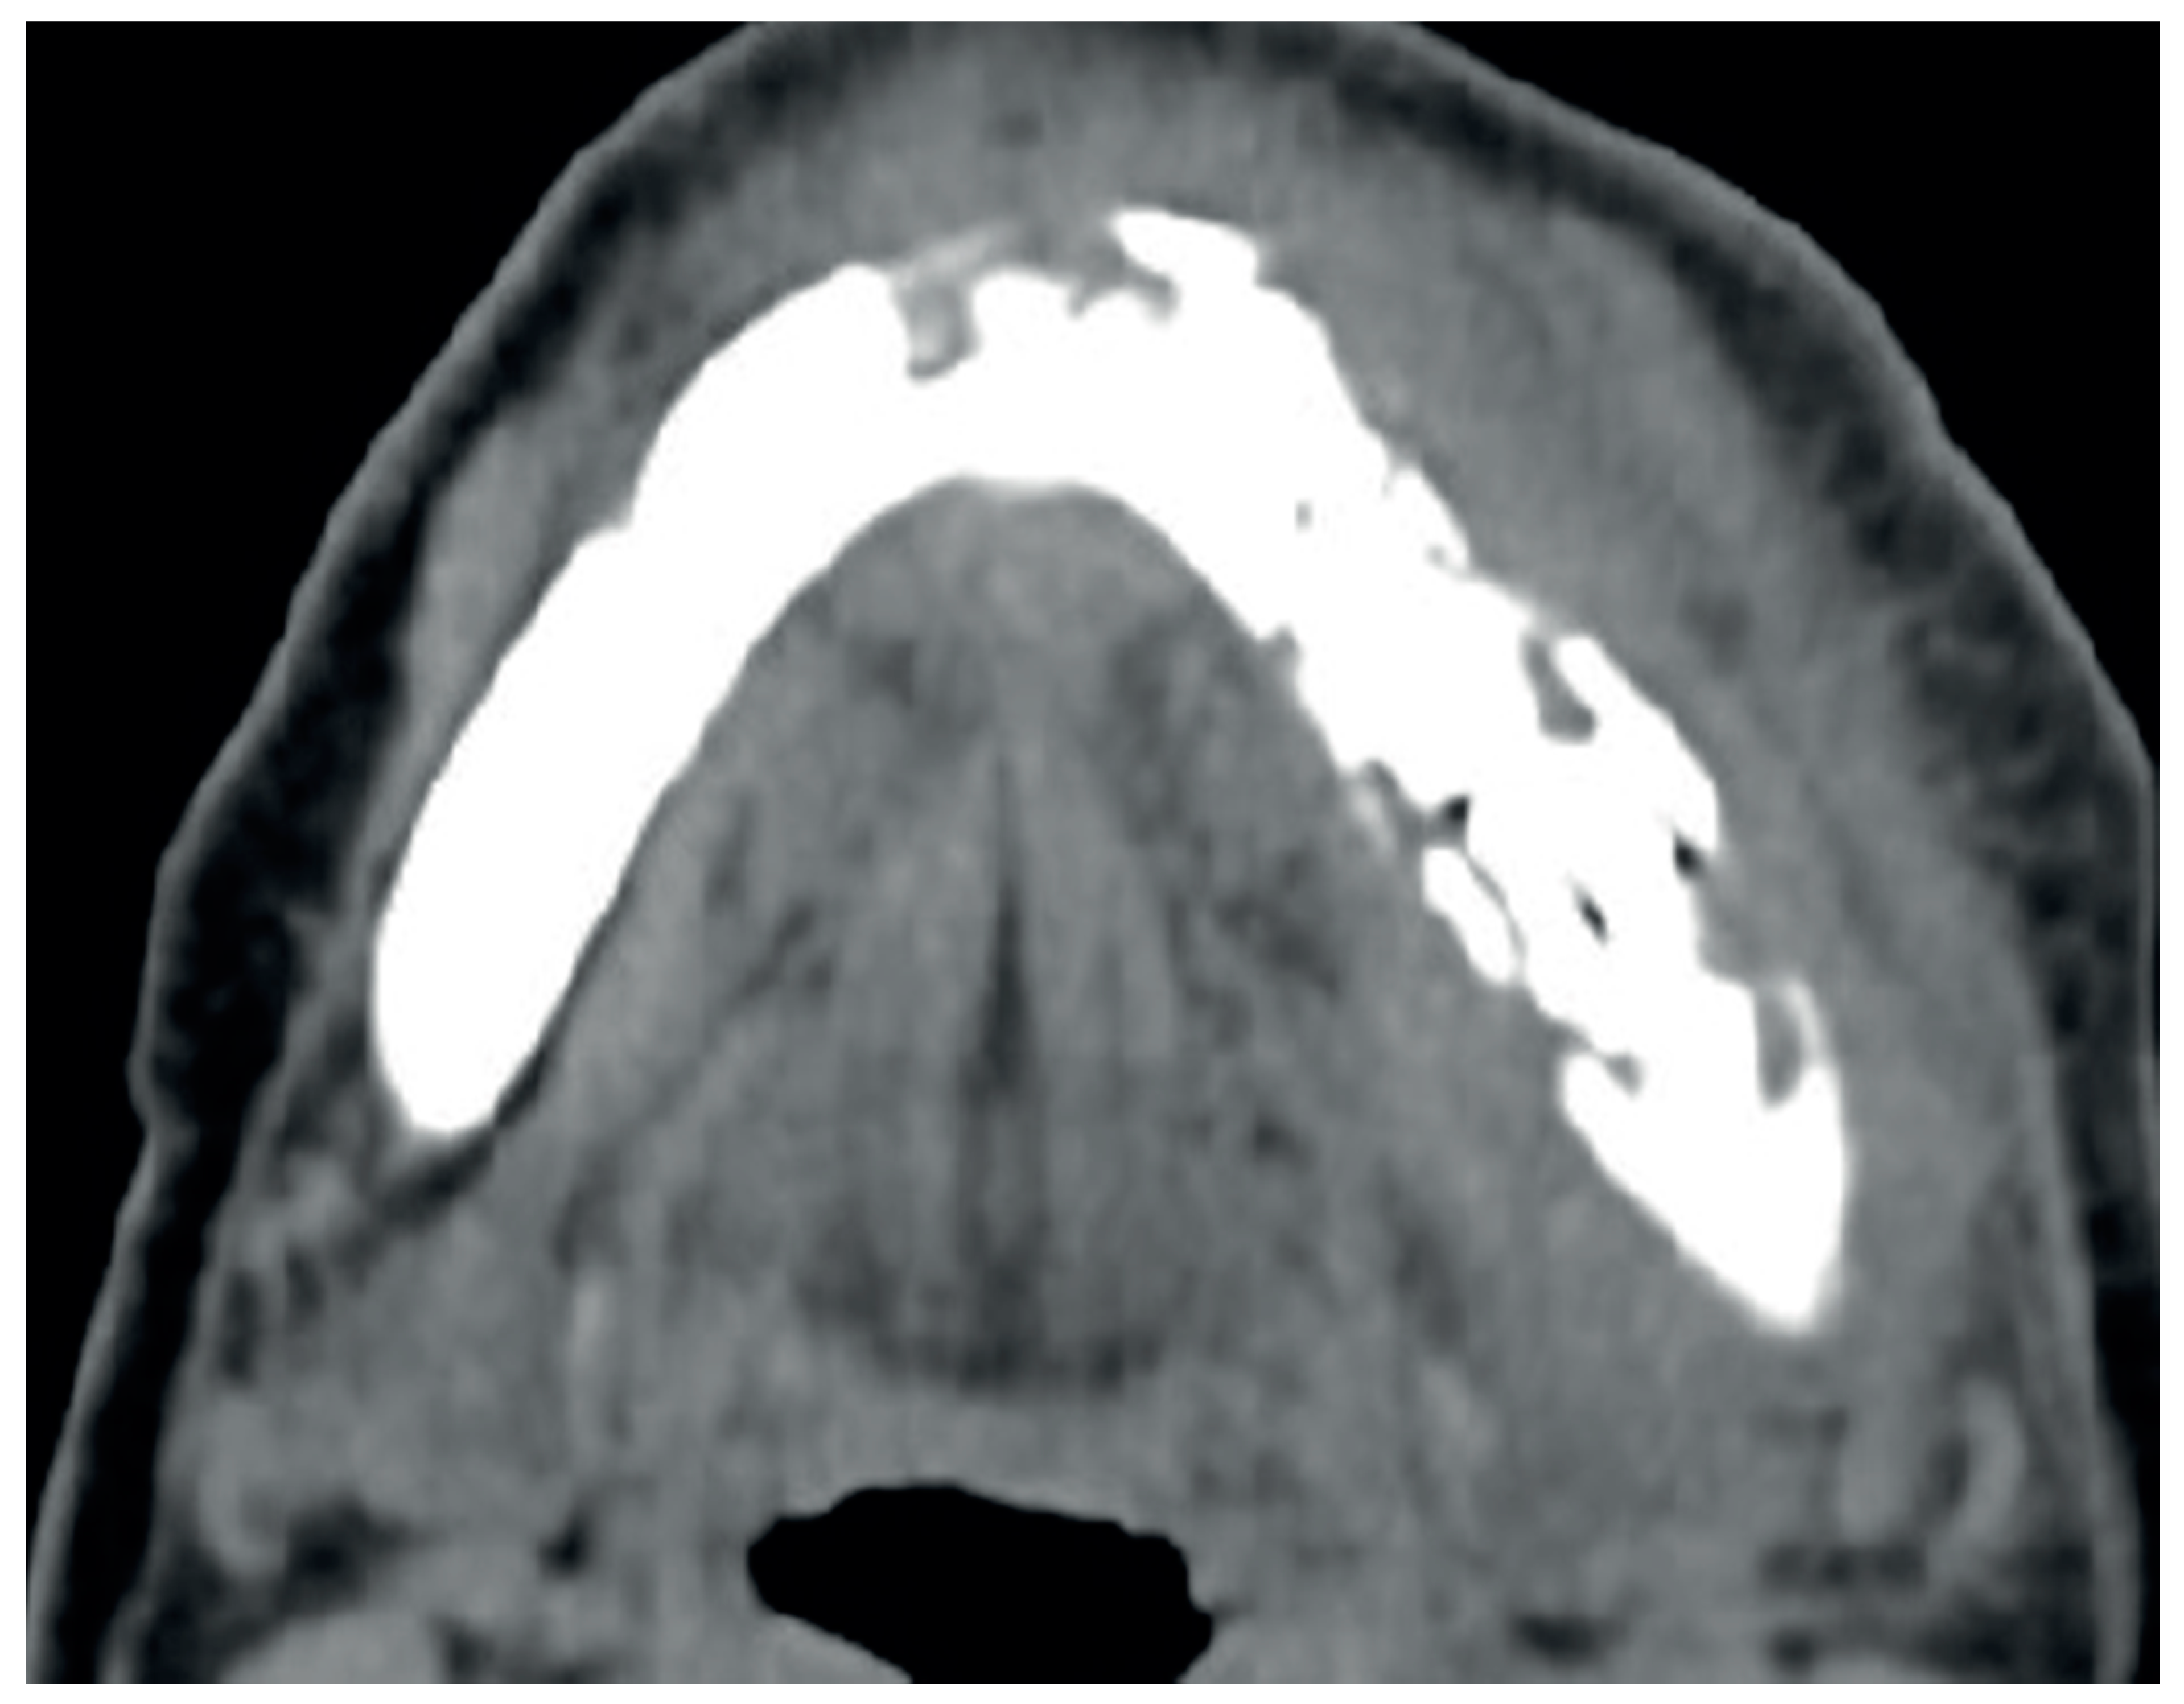

2.4. Diagnostic Assessment